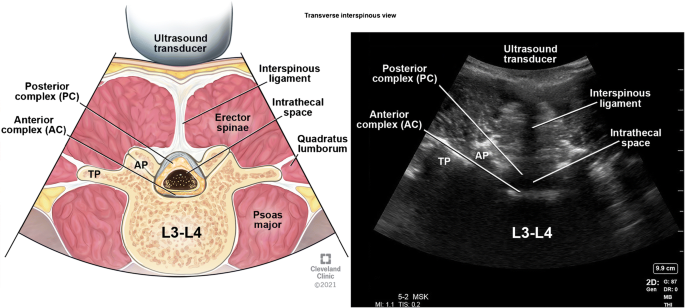

The ligamentum flavum, epidural space, and posterior dura often appear as single or sometimes double hyperechoic white structure referred to as the posterior complex (PC). The anterior dura, posterior longitudinal ligament, and the posterior aspect of the vertebral body are visible as a single hyperechoic white line referred to as the anterior complex (AC). The anterior and posterior complexes can be visualized in both interlaminar and interspinous views with the thecal sac in between.

Transverse Interspinous View

After identification of the spinous process, the probe is either moved cephalad or caudad to the interspinous space (Fig. 5 probe position B). This view, also known as the transverse interlaminar view, allows for visualization of the posterior and anterior complexes along with articular and transverse processes laterally (Fig. 15). The depth of the posterior complex from the skin can be noted in this view and is useful for guiding epidural placement. The angle of the probe required to visualize posterior and anterior complexes in this view facilitates the angle of incidence for needle entry for successful neuraxial placements. After identification of posterior and anterior complexes, the ink markings are made in horizontal and vertical directions are joined together to mark the entry point for neuraxial procedures (Figs. 17 and 18). The intrathecal space is seen as hypoechoic space between the posterior and anterior complexes. An un-obstructed interlaminar space is a space where both the posterior and anterior complexes can be clearly visualized. The widest, unobstructed interspace can be used for access to the neuraxis. This is done by sliding the ultrasound transducer caudad and cephalad in the transverse interspinous process view. Maintaining the visibility of the anterior complex for a larger distance indicates a wider interspinous space.

Fig. 15

Transverse interspinous view. (This image is produced with permission from Cleveland Clinic Center for Medical Art & Photography)